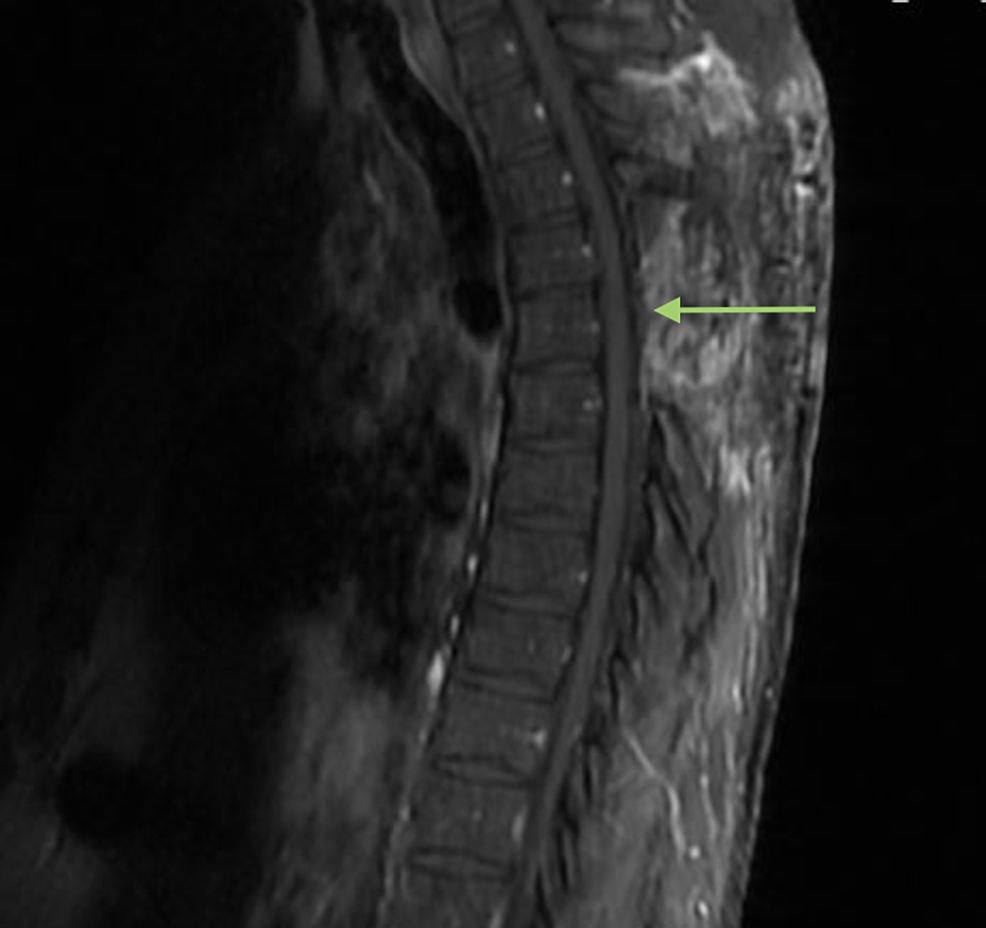

The foremost objective of peer review is the promotion of the highest quality of patient care Peer review is one of the most respected activities in quality assurance and total quality management RadNet’s peer review program helps ensure that our radiologists are competent and practice within the boundaries of professionally accepted norms. The Gulf of Mexico Research Initiative (GoMRI) will select awards for funding by merit review based on peer evaluation, modeled after the National Science Foundation’s Peer Evaluation Process An administrative review of the preliminary and full proposals will take place to ensure that each proposal follows the proposal submission. Radiographers manipulate many parameters during MRI examinations, and image quality can be degraded if sequences are not optimised This may lead to misinterpretation Initial results suggest peer review can result in improved image quality, better protocols, and improved staff confidence There are opportunity costs involved in releasing staff from clinical work and time and resources required for image appraisal training, however we suggest this model can be extended to other departments.